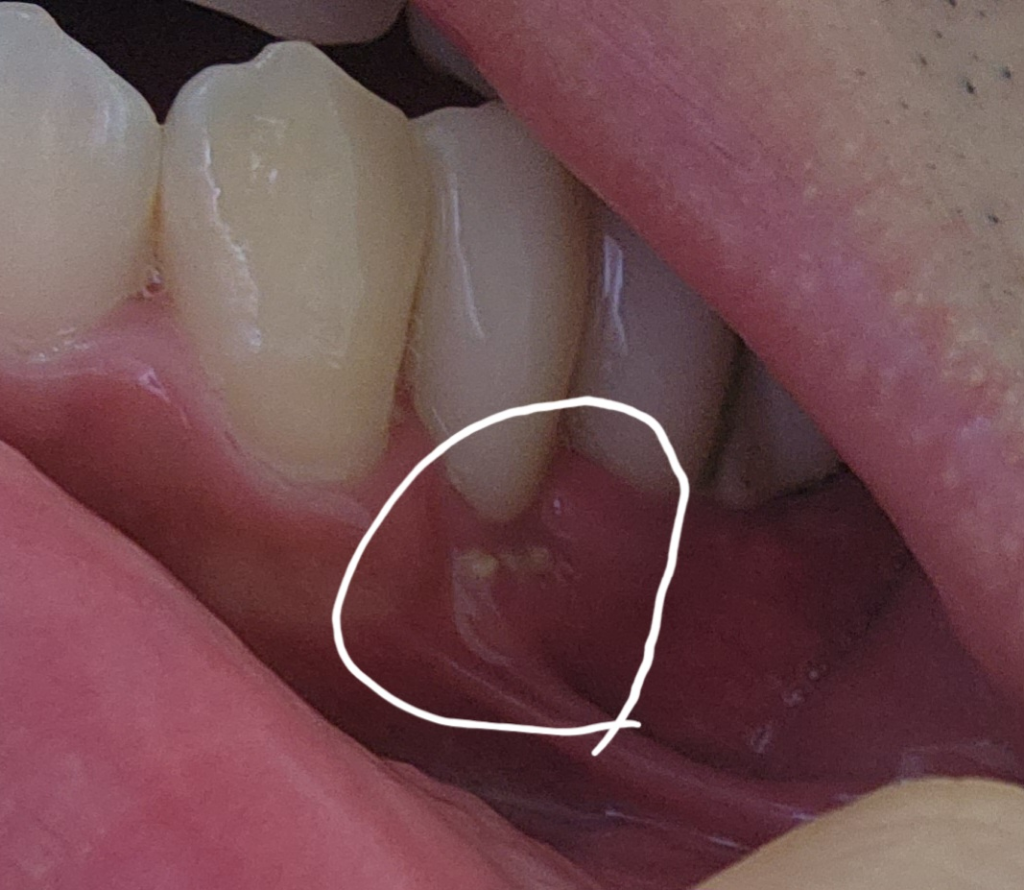

임플란트 보철까지 마친 상태에서 잇몸뼈 노출

이번년도 1월정도에 임플란트 보철까지 진행 하였는데 얼마전 잇몸을 확인하니 뼈이식 했을때 보였던 뼈이식조각들이 잇몸에 살짝씩 노출되어 있는게 확인 되는데 이런경우는 어떻게 해야 할까요?

임플란트 수술한 치과의 말만 듣는것 보단 치과에 방문전 관련 정보를 알고 방문해서 의사선생님과 상의하는게 좋을것 같아서 문의드립니다.

• 1번 째 사진

골 이식을 하고 나서도 골화가 되지 않은 골 이식재는 잇몸 밖으로 나올 수 있습니다. 크게 문제가 되진 않지만 해당 부위를 자극하지 않는 것이 좋습니다. 또한 자세한 확인을 위해서 치과에서 진료를 받아보는 것이 좋습니다

사진에 보이는건 뼈이식재료는 아니거 같고 부골인거 같습니다. 잇몸뼈가 과하게 증식되서 튀어 나온거 같으니 마취후에 제거를 하면될것같습니다 .